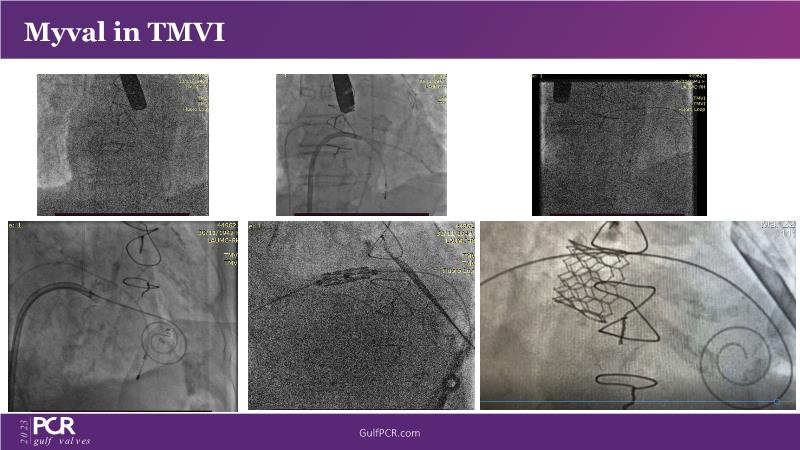

This session is a valuable resource for grasping innovative strategies in handling bifurcation and extended diffuse lesions through dedicated stenting solutions. Explore insights into the advanced Myval next-generation THV technology, unveiling its distinctive features, procedural advantages, and clinical outcomes across a diverse patient pool. Gain understanding into the CorAlign technique, ensuring accurate commissural and coronary alignment while maintaining coronary access. Additionally, delve into the techniques for precise sizing, positioning, and deploying of Myval THV.

- To understand the technique of precise sizing, positioning and deployment of Myval THV